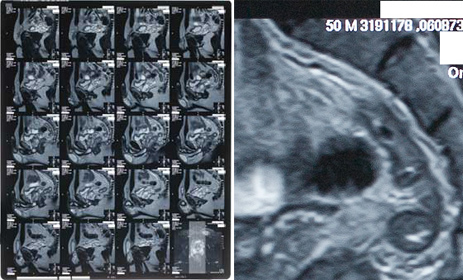

※画像:複写した放射線フィルムの部分拡大

保全撮影したカルテ、レントゲン類をCD一枚で閲覧することができ、保管もコンパクトで大変便利です。レントゲン、CT、MRI画像は細部まで鮮明に再現するためより詳細な検証にご活用いただけます。 CD内のPDFデータをタブレット端末に移したことで法廷内で役にたった、との声もいただいております。